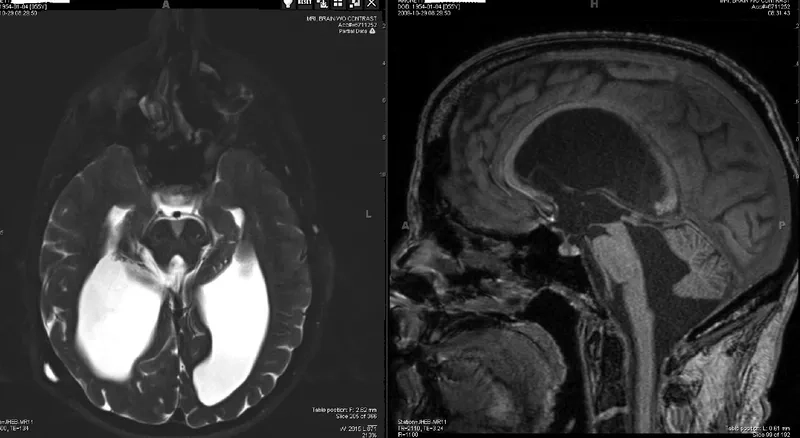

MRI brain scan showing enlarged ventricles in NPH